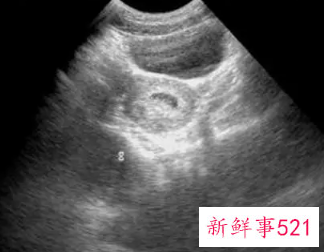

B超检查只能在妊娠5周后可以看见孕囊,妊娠6周时妊娠囊检出率达100%。妊娠6—7周可见胚芽,孕49天,胚芽径线2mm时可见原始心管搏动,妊娠8周初具人形。

女性在怀孕初期的时候,必须要做一次B超,了解胎儿发育情况,也是排除宫外孕的可能。一般女性在怀孕第7周的时候,做B超检查是最佳时间,女性怀孕6周的时候,可以确认孕囊着床位置。在怀孕7周的时候,可以检查出胎心,超过7周还没有胎心,基本上就停止发育了。

B超也不能做的太早,怀孕不满6周的`时候做B超,孕囊还太小看不出来位置在哪里。女在做腹部B超检查前需要憋尿,检查前要先预约好时间,憋尿不能憋过头。女性怀孕多少周可以看B超确认,月经周期在28天到30天来的女性。